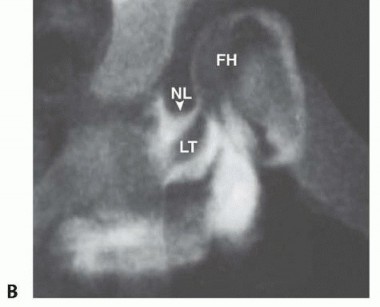

3. ## Proximal Femoral Shortening Osteotomy

A straight lateral approach to the proximal femur is used. The tensor fascia is divided longitudinally.

The anterior edge of the gluteus medius muscle is identified where it attaches to the greater trochanter. Several millimeters of the gluteus medius muscle is detached off the trochanter.

This allows palpation of the anterior aspect of the femoral head to estimate the amount of femoral torsion (

TECH FIG 3A

).

The vastus lateralis muscle is detached off the femur by dividing its proximal attachment in the transverse plane at the trochanteric ridge, leaving enough cartilage attached to the muscle to allow secure fixation during closure (

TECH FIG 3B

The vastus lateralis muscle should be divided off the posterior intermuscular septum so that the muscle innervation is left completely intact.

Stiff Steinmann pins are inserted in the proximal and distal femur to ensure that a proper amount of femoral rotation is provided.

A third pin is placed up the neck of the femur to judge femoral head-neck antetorsion, and a fourth pin is placed just below the lesser trochanter to guide the osteotomy.

A one-third tubular small fragment plate or a 2.7-mm minifragment dynamic compression plate is generally sufficient in a young child (

TECH FIG 3C

). A 3.5-mm dynamic compression plate is used for an older child.

The proximal aspect of the plate is fixed loosely.

A subtrochanteric osteotomy is believed to be less hazardous to the hip vascularity than an intertrochanteric osteotomy.

The femur is shortened by the amount that the cut ends of the femur overlap when the femoral head is reduced (

TECH FIG 3D

The shortened fragment of femur can be used for holding open a pelvic osteotomy.

TECH FIG 3

•

A.

About 5 mm of the most anterior edge of the gluteus medius muscle is detached from the greater trochanter so that the femoral neck can be palpated and visualized (shown on a left hip).

B.

The vastus lateralis muscle is detached from the trochanteric ridge (

TR

) and the posterior intermuscular septum (

IS

) to expose the proximal femur (

F

C.

A one-third tubular plate has been attached to the proximal femur, and a 2-cm segment of bone has been removed from the subtrochanteric aspect of the femur.

D.

The femur has been shortened, rotated into less antetorsion, and compressed.

E.

The tension

band of the vastus lateralis muscle is reestablished with 0 absorbable suture.

The plate is prebent slightly and is secured with some compression applied.

The Steinmann pins are used to judge any rotation that is desired.

If excessive femoral torsion was noted, some of this can be judiciously corrected. The tension band effect of the vastus lateralis muscle is restored (

TECH FIG 3E

). The incision is closed with absorbable suture. No drain is necessary.